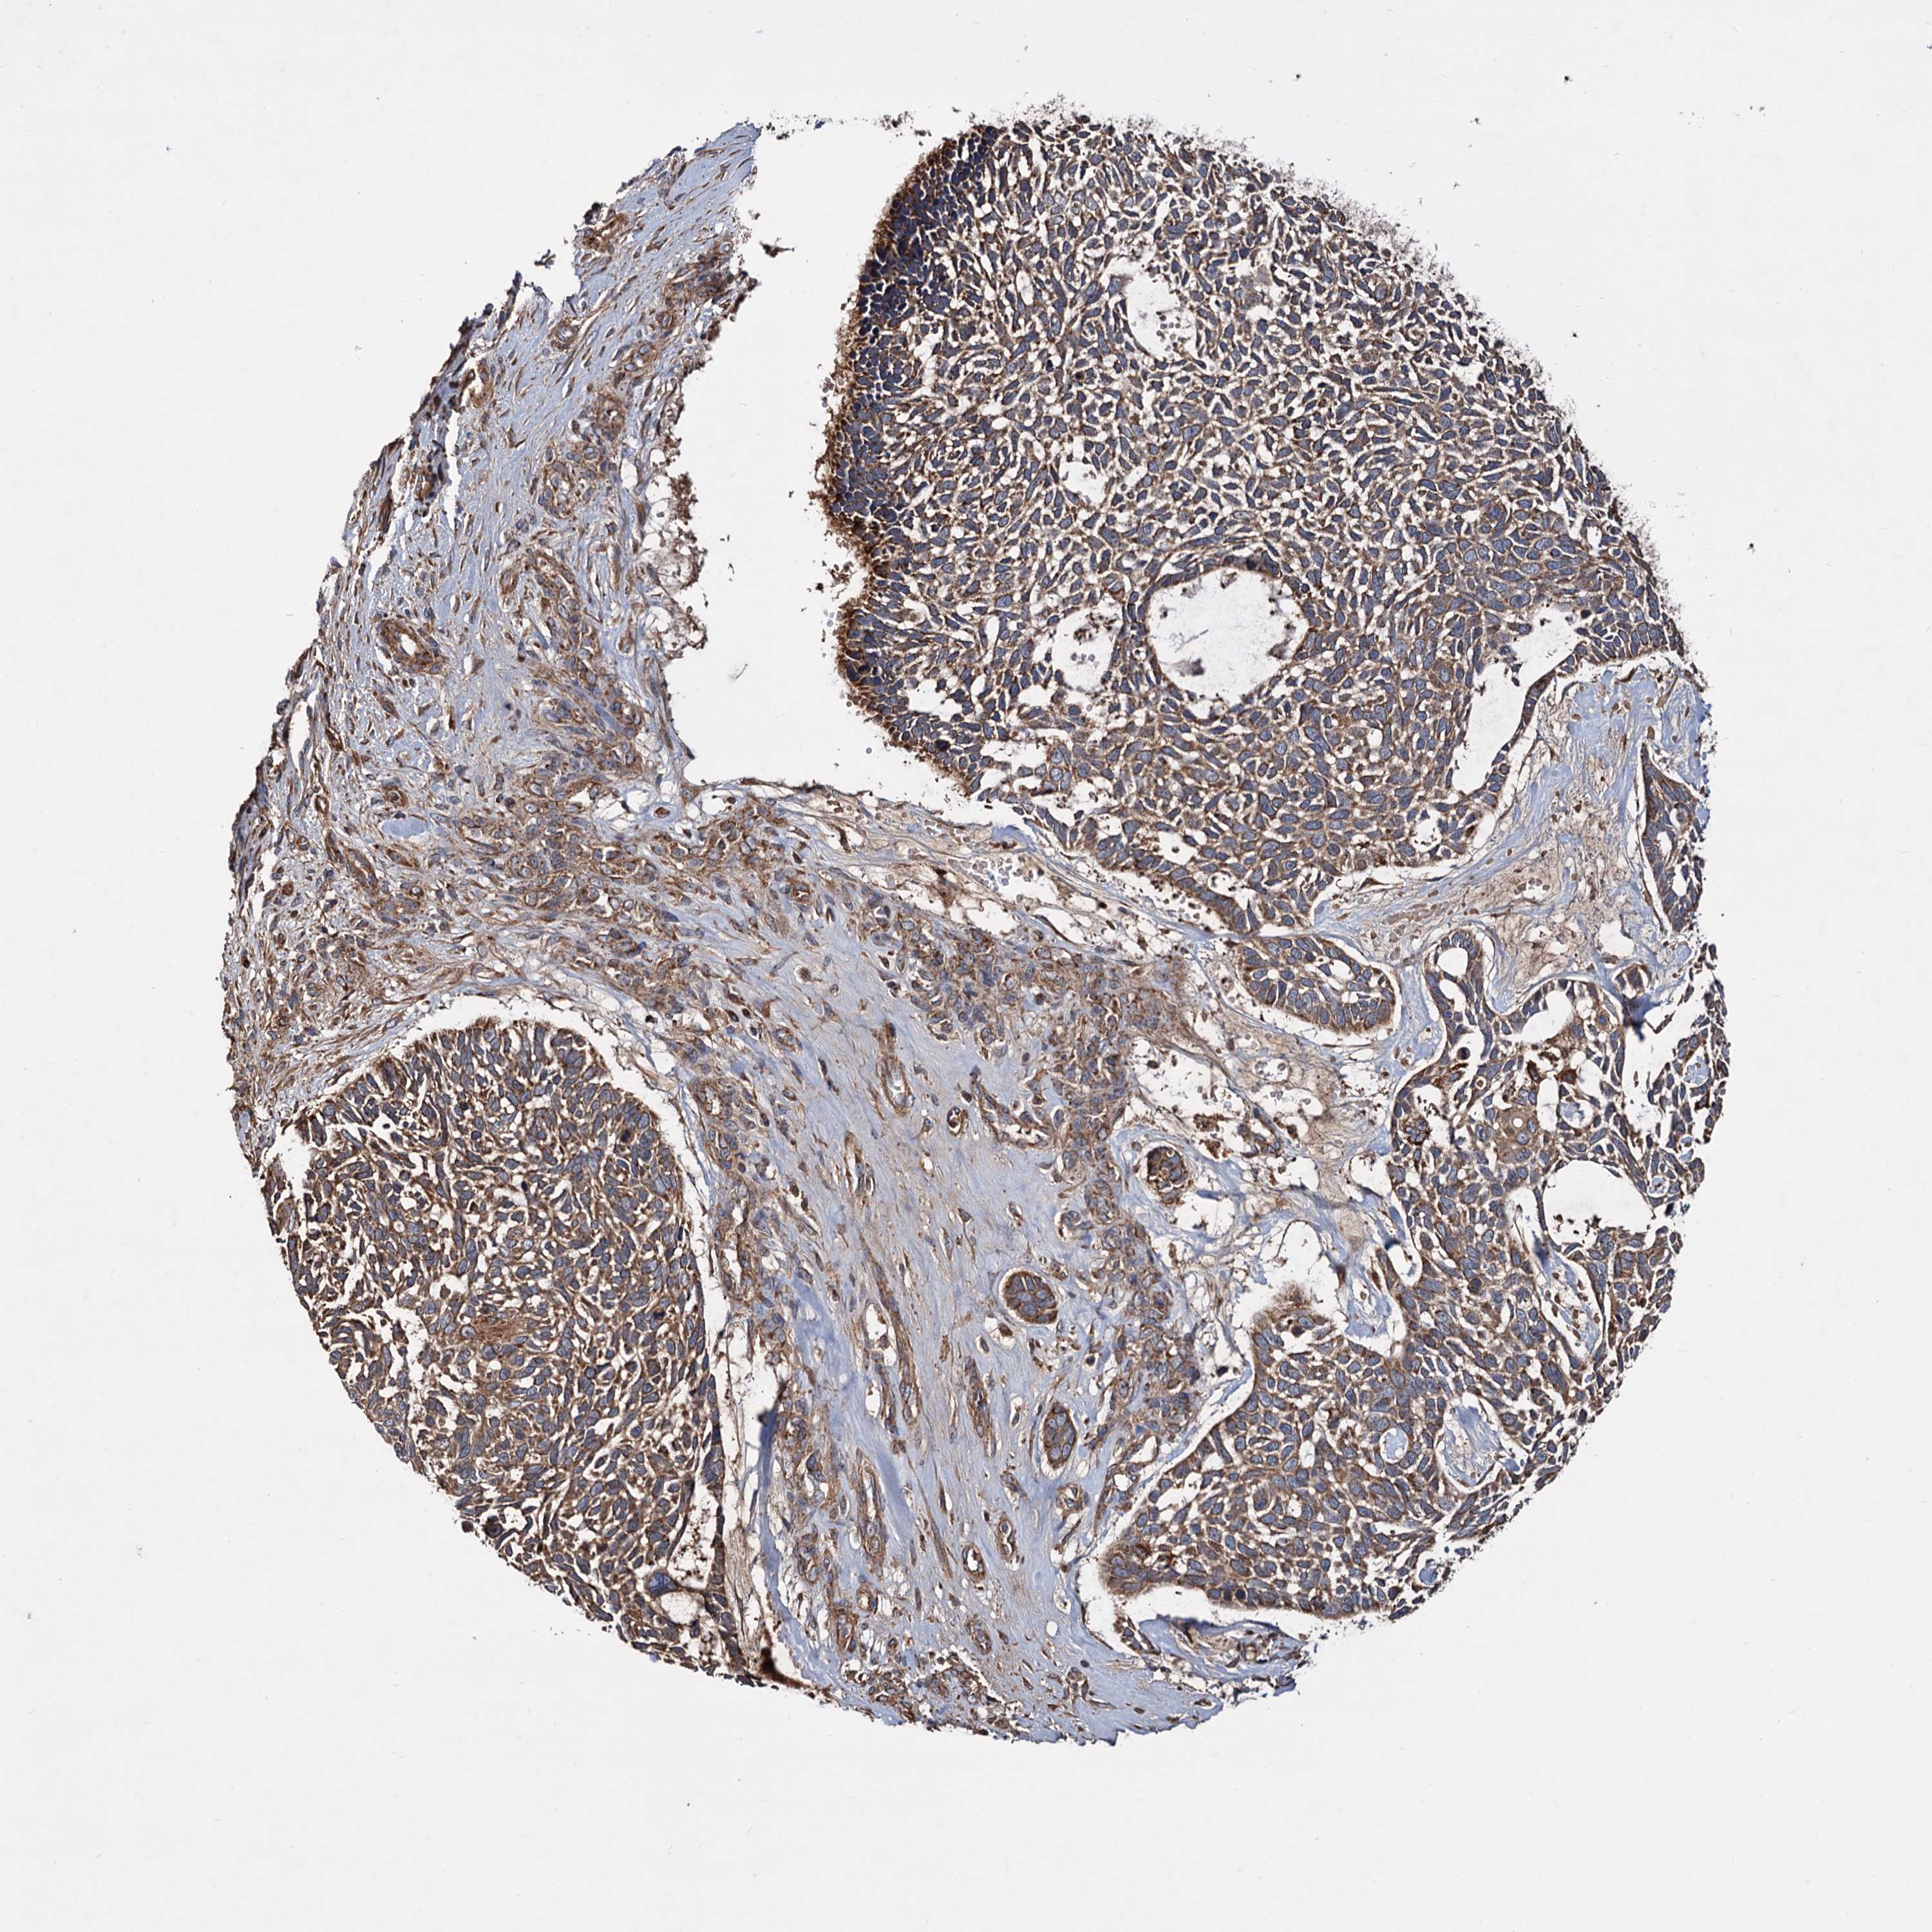

SKIN CANCER - Protein expressioni

A mouse-over function shows sample information and annotation data. Click on an image to view it in a full screen mode. Samples can be filtered based on level of antibody staining by selecting one or several of the following categories: high, medium, low and not detected. The assay and annotation is described here.

Antibody stainingi

Antibody staining in the annotated cell types in the current human tissue is reported as not detected, low, medium, or high, based on conventional immunohistochemistry profiling in selected tissues. This score is based on the combination of the staining intensity and fraction of stained cells.

Each image is clickable and will lead to virtual microscopy that enables deeper exploration of all samples and also displays staining intensity scores, fraction scores and subcellular localization as well as patient and tissue information for each sample.

Antibody HPA039398

Staining

High

Medium

Low

Not detected

Intensity

Strong

Moderate

Weak

Negative

Quantity

>75%

75%-25%

<25%

None

Location

Nuclear

Cytoplasmic/membranous

Cytoplasmic/membranous,nuclear

Basal cell carcinoma